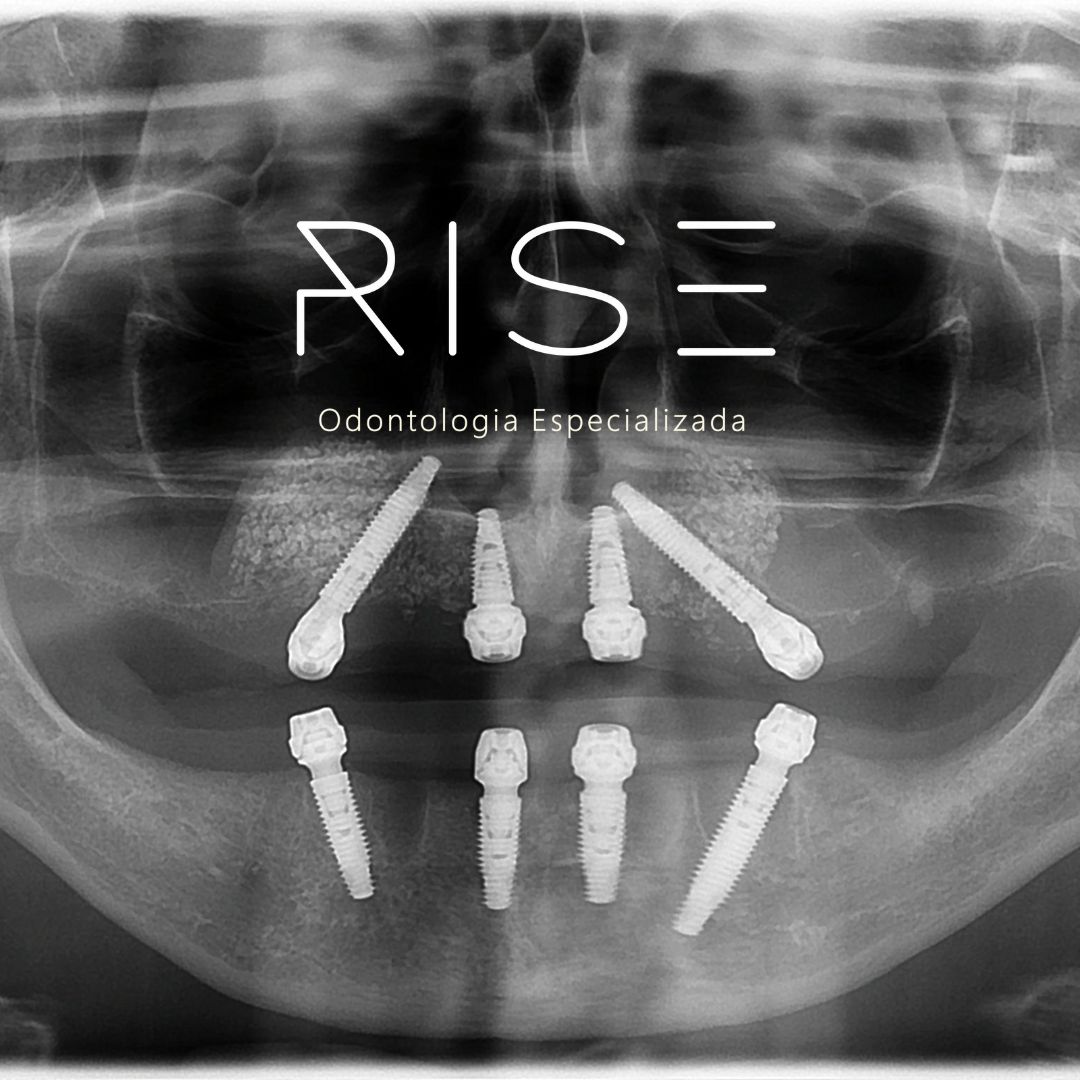

São quatro implantes posicionados de forma estratégica. Com esta técnica, o enxerto ósseo não é necessário, já que o objetivo desta técnica é maximizar o aproveitamento do osso para minimizar a necessidade de enxerto ósseo. Com a PRÓTESE PROTOCOLO ALL-ON-FOUR o procedimento se torna mais rápido, econômico, eficaz, menos invasivo e menos traumático.

Aqui na Clínica Rise Odontologia em Balneário Camboriú, é possível ter a prótese fixa instalada imediatamente, dependendo muito do caso do paciente. A técnica ALL-ON-FOUR permite devolver dentes fixos ao paciente tanto na arcada superior quanto inferior.

Para a realização deste procedimento, um dos exames solicitados é a tomografia computadorizada, que é um exame bem completo onde o cirurgião dentista consegue ver a altura e espessura do seu osso.